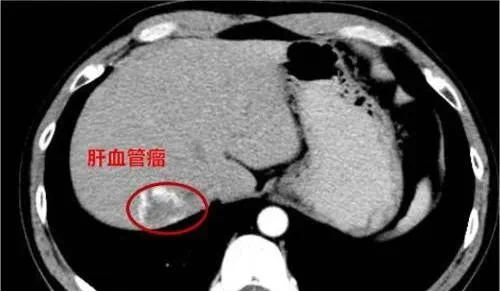

不过,以上这种肉眼观察或光影测试,只能作为血管瘤初步怀疑的依据。毕竟,还有部分血管瘤“藏得很深”,位于深部肌肉或器官内,比如:

长在肝脏内的血管瘤,可能压迫肝内胆管,导致胆汁排泄不畅,引起黄疸;